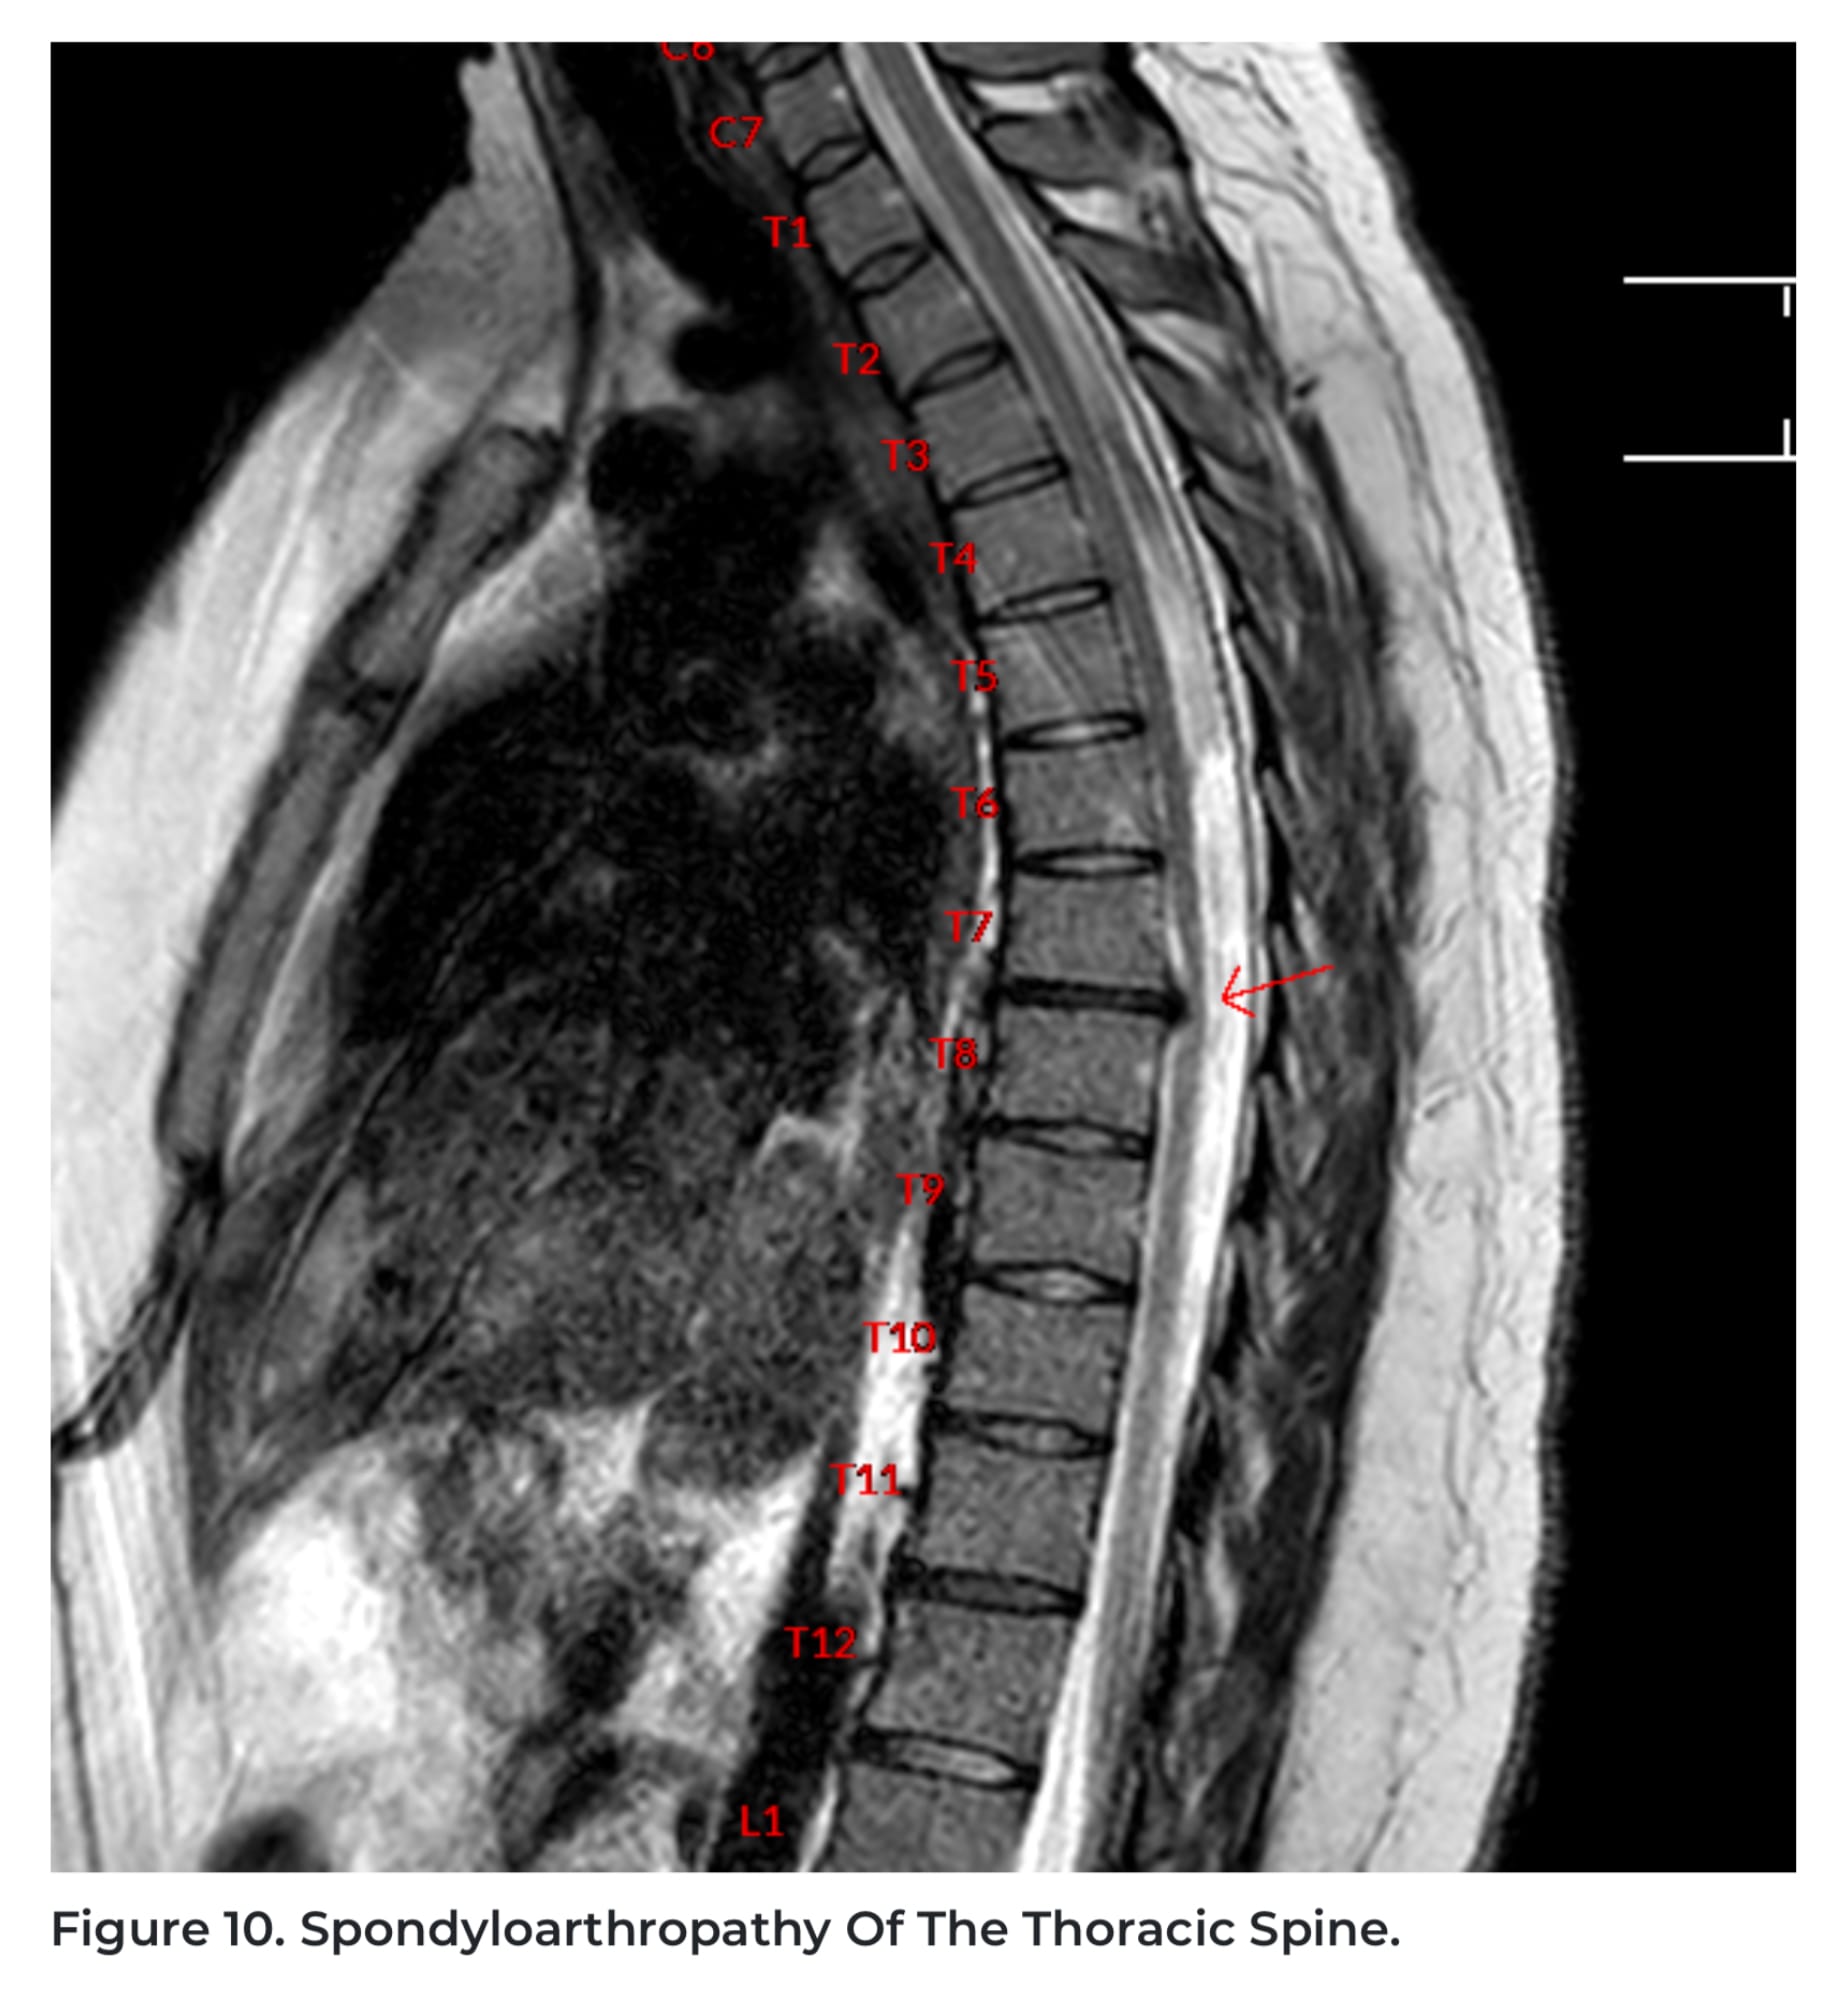

The GIF at the top is one of the image styles they show. Below is a beautiful shot of the arthritis in my spine.

If you’ve seen typical MRI scans before, you know they can be grainy or confusing. These were clear, well-labeled, and even interactive. I always request copies of my scans for my doctors, and these put every past scan I’ve had—no matter the cost—to shame.